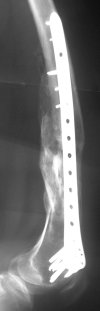

1. Percutaneous nailing is truly minimally invasive technique, but, unfortunately, nails are not reliable in many hands.

Attached are few examples from our Hospital:

A. Difficult reductions, even in retrograde nailing (my preference, easier control of "small" distal fragment) and it is much, much harder to do it anterograde (Alex, do you have one good case in your collection of anterograde nailing in very distal fractures - as you have suggested that I

should have done it in my previously posted case?

Malpositioning is much too common (recurvatum, varus - valgus).

B. Fixation loosening: distal cutting of the nail, non-unions do happen (cases attached).

Locking Plating has more distal screws than any nail, fixed angles and provides much better fixation, especially in osteoporotic bone.

A new toy is more interesting and fashionable. And anyway it is not panacea, i have already seen presentations with LISS failures like the attached one presented by D.Seligson. And people also demonstrated incisions say that the method is not so LESS invasive as it supposed to be.